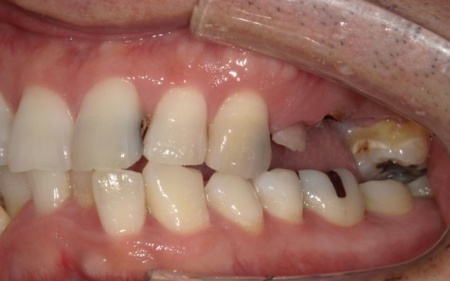

40代男性 温存が難しい複数の歯を抜いてインプラントブリッジで修復した症例

「ブリッジが外れたまま放置していた。また、前歯が欠けているのが気になる」とご相談いただきました。

拝見したところ、上左右の奥歯には、歯が失われていたり欠けたりしている部位が複数確認されました。

患者様によると、以前上顎にはブリッジ(両隣の歯を支えとして欠損部を補う装置)が装着されていましたが、10年前に外れたきりそのままの状態で過ごしていたとのことでした。

痛みがなかったため、とくに治療は受けていなかったようですが、以前から前歯の一部が欠けていることが気になっており、見た目や将来のお口の健康に不安を感じていたそうです。

そこで、詳しく検査を行った結果、欠けたり傷んだりしている歯が複数見つかり、さらに歯茎や歯を支える骨にも問題が生じていました。

とくに、右上奥歯は前から4番目と6番目の歯、左上奥歯は前から4番目・5番目・6番目・8番目の歯が著しく傷んでおり、温存が難しいと考えられます。

また、右下の一番奥の歯(親知らず)は歯の根だけが残り、細菌感染が広がるリスクが高い状態です。

その一方で、上前歯や右下奥歯は、適切な処置を行うことで温存できる歯も複数確認できました。